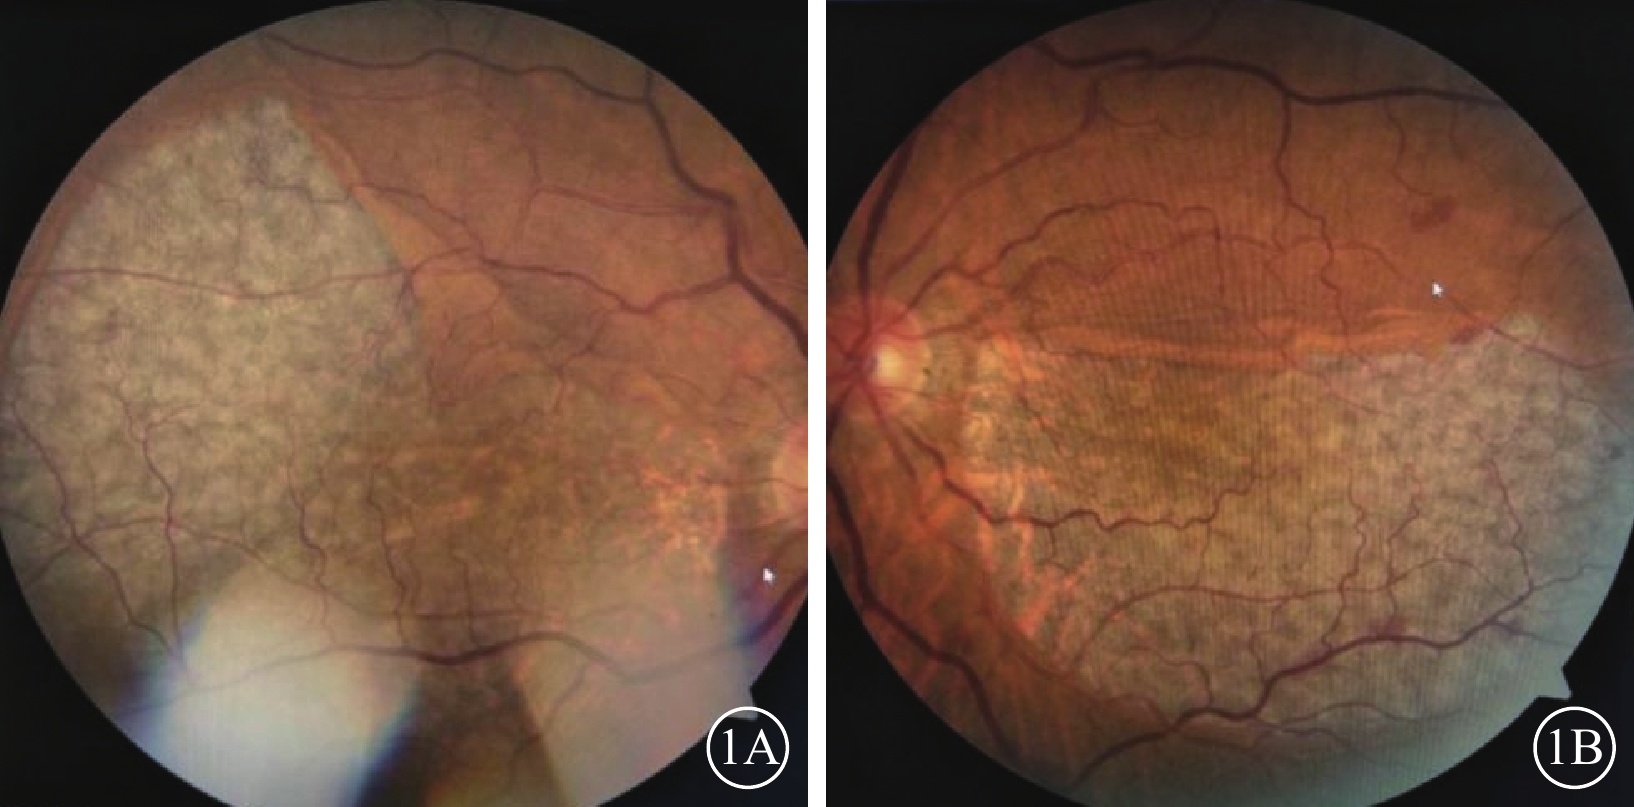

患者女,68歲。因雙眼視物模糊20 d于2018年3月20日來我院眼科就診。既往肺心病10年;否認雙眼外傷史,否認遺傳病家族史。眼部檢查:雙眼視力0.1,均不能矯正。右眼眼壓16 mmHg(1 mmHg=0.133 kPa),左眼眼壓15 mmHg。雙眼眼前節檢查正常。眼底檢查,雙眼后極部巨大RPE撕裂,撕裂區透見脈絡膜水腫;上方RPE收縮卷曲皺褶;視網膜血管紆曲(圖1)。OCT檢查,后極部撕裂區RPE信號消失。對應RPE卷曲皺褶處強反射隆起信號。未撕裂范圍RPE信號正常(圖2)。因患者原因未行FFA檢查。臨床診斷:雙眼特發性RPE撕裂。

圖1

雙眼彩色眼底像。1A示右眼,后極部巨大不規則形RPE撕裂,上方可見皺褶隆起。隆起處視網膜血管呈爬坡樣;1B示左眼,后極部半月形撕裂區,上方RPE收縮卷曲,視網膜小靜脈有毛刷樣出血

圖1

雙眼彩色眼底像。1A示右眼,后極部巨大不規則形RPE撕裂,上方可見皺褶隆起。隆起處視網膜血管呈爬坡樣;1B示左眼,后極部半月形撕裂區,上方RPE收縮卷曲,視網膜小靜脈有毛刷樣出血

患者女,68歲。因雙眼視物模糊20 d于2018年3月20日來我院眼科就診。既往肺心病10年;否認雙眼外傷史,否認遺傳病家族史。眼部檢查:雙眼視力0.1,均不能矯正。右眼眼壓16 mmHg(1 mmHg=0.133 kPa),左眼眼壓15 mmHg。雙眼眼前節檢查正常。眼底檢查,雙眼后極部巨大RPE撕裂,撕裂區透見脈絡膜水腫;上方RPE收縮卷曲皺褶;視網膜血管紆曲(圖1)。OCT檢查,后極部撕裂區RPE信號消失。對應RPE卷曲皺褶處強反射隆起信號。未撕裂范圍RPE信號正常(圖2)。因患者原因未行FFA檢查。臨床診斷:雙眼特發性RPE撕裂。

圖1

雙眼彩色眼底像。1A示右眼,后極部巨大不規則形RPE撕裂,上方可見皺褶隆起。隆起處視網膜血管呈爬坡樣;1B示左眼,后極部半月形撕裂區,上方RPE收縮卷曲,視網膜小靜脈有毛刷樣出血

圖1

雙眼彩色眼底像。1A示右眼,后極部巨大不規則形RPE撕裂,上方可見皺褶隆起。隆起處視網膜血管呈爬坡樣;1B示左眼,后極部半月形撕裂區,上方RPE收縮卷曲,視網膜小靜脈有毛刷樣出血